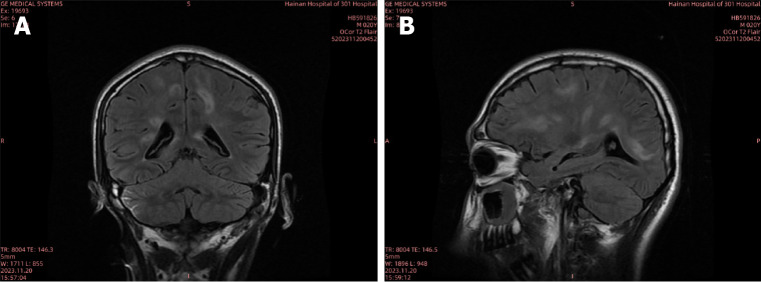

Case summary: A 20-year-old male developed persistent neck and back pain after consuming raw snail meat, followed by urinary retention and low fever. After admission, the patient was misdiagnosed as viral infection and Mycobacterium tuberculosis in central nervous system. After detection of Angiostrongylus cantonensis in blood and cerebrospinal fluid by metagenomics next generation sequencing, albendazole was administered with ceftriaxone and methylprednisolone treatment simultaneously. With effective antiparasitic treatment, the patient weaned from mechanical ventilation successfully and transferred out of intensive care unit for hyperbaric oxygen and rehabilitation treatment.